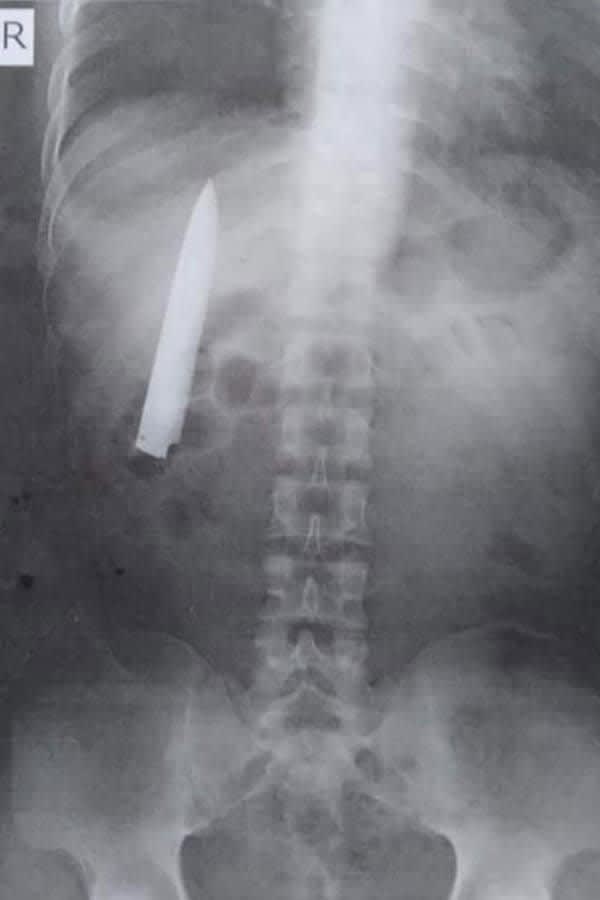

レントゲン撮ったら胸にナイフが 寒い日はズキズキしておかしいと Daily Sun New York